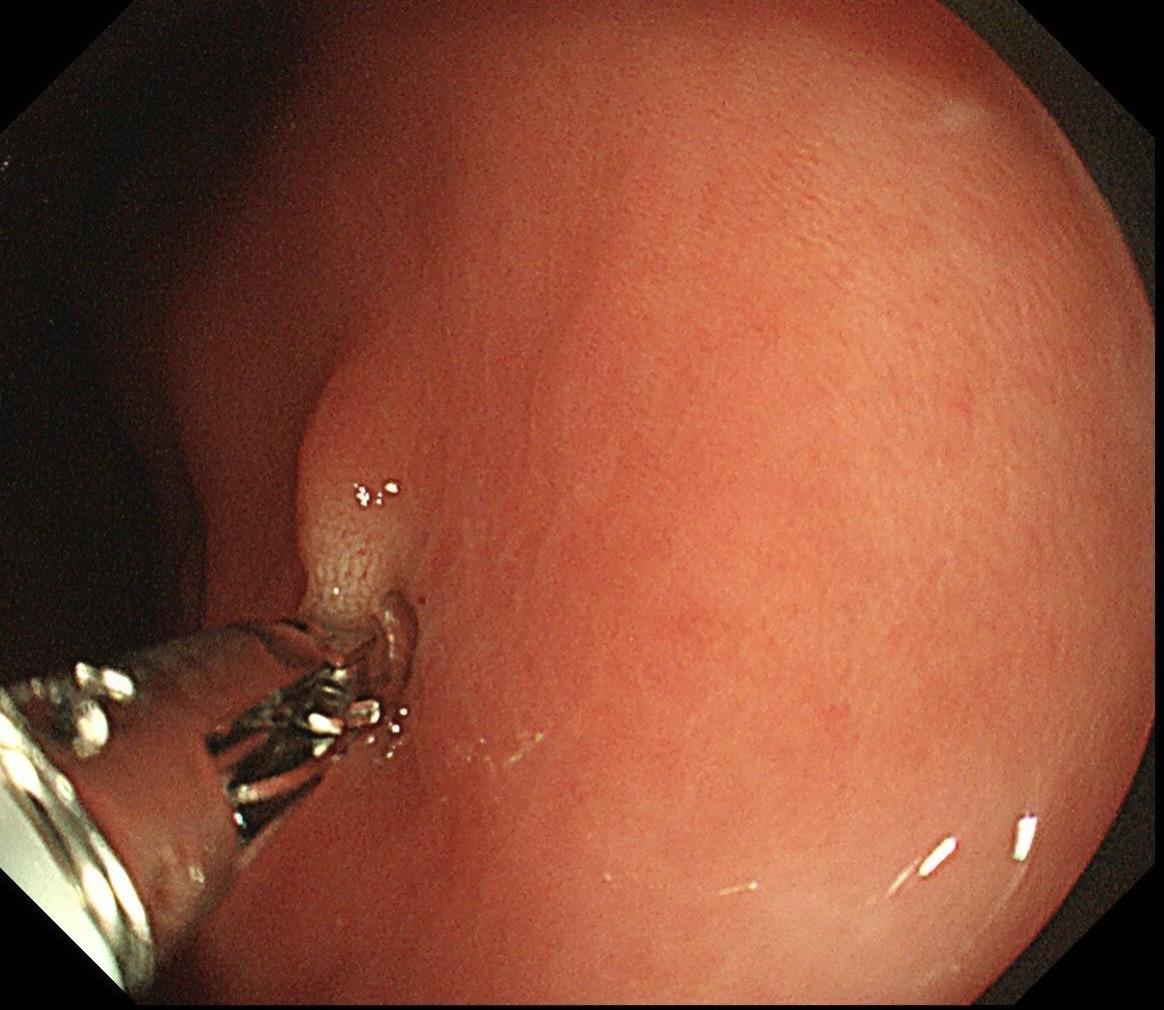

男,40岁,胃双发褪色调病变。慢性胃炎复查,3年前胃镜未见异常,Hp阳性背景,萎缩不明显,胃体下部大弯见一褪色调病变,浅凹陷,5mm左右,换用放大内镜观察,表面结构缺失,血管异型明显,未分化可能性大……胃窦后壁见一白斑,无高度差,NBI浅茶色,放大草草看了下,似有边界,IP增宽,活检待病理……小哥哥胖得几乎没脖子,腹式呼吸太明显~😖